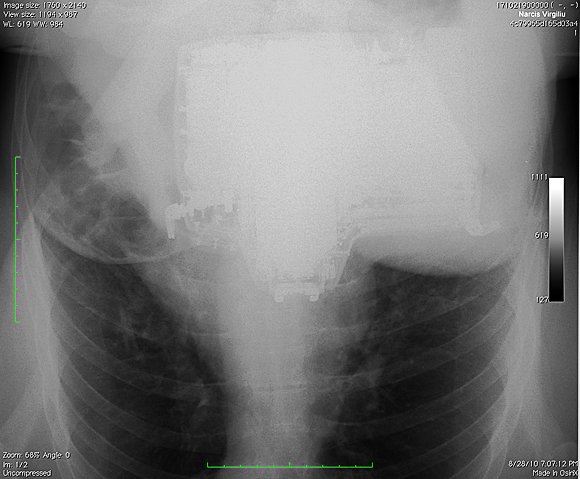

Ma tot gandesc de ceva timp la o noua schimbare pentru fotografiile de la biografie si m-am decis, intr-un fel anume, diferit de imaginile clasice, RADIOGRAFII . Radiografia este ruda cu fotografia, dex-ul spune ca ea reprezinta fotografierea interiorului unui corp opac, in special a unor regiuni din interiorul corpului omenesc sau animal, cu ajutorul razelor x, practic, conform dex-ului, va prezint mai mult… A patra din pacate nu a iesit cum imi inchipuiam aparatul de fotografiat fiind oarecum estompat din cauza unghiului prost ales, din pacate nu am putut s-o refac deoarece 3 radiografii/zi inseamna o cantitate suficient de mare de radiatii.

p.s. Am completat cu o panoramica dentara, cu un RMN la coloana si cu doua radiografii cervicale. Seria continua !